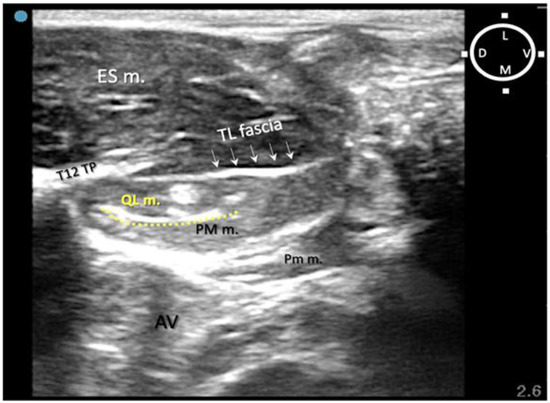

Figure 2. Ultrasound-guided quadratus lumborum block (QLB) performed using a ventromedial approach. (A) Sono-anatomy of the thoracolumbar area at the level of the twelfth thoracic vertebra transverse process, arrows pointing out the thoracolumbar fascia, hyperechoic line. (B) In a different rabbit cadaver, the QLB was performed, using the ventromedial approach injecting a mixture of lidocaine 2%, permanent yellow tissue dye and iodine contrast (3:1:1). The needle is visible on the ultrasound image travelling close to the right kidney (RK). (C) After anatomical dissection, in the same rabbit of (B), the right kidney was exposed and part of the mixture was found in the kidney capsule after injection. ES m. erector spinae muscles; D dorsal; L lateral; M medial; PM m. psoas major muscle; Pm m. psoas minor muscle; QL m. quadratus lumborum muscle; RK right kidney; T12 TP transverse process of the twelfth thoracic vertebra; V ventral. Cyan blue dot indicates the marker of the ultrasound probe pointed dorsally.

The first two out of four rabbit cadavers were used to understand the sono-anatomy and the relationship of the quadratus lumborum muscle and the thoraco-lumbar fascia surrounding the quadratus lumborum muscle and psoas muscles, and to design an ultrasound-guided quadratus lumborum muscle block approach specific for rabbits. For the needling, a ventral approach as reported in dogs and cats was first used [16,17] with the needle directed from the ventro-lateral to dorso-medial. However, during the sono-anatomy study, the abdominal structures such as the kidney and liver were very close to the needle path, resulting in an increased risk of potential internal organ damage (Figure 2A,B). Those concerns were confirmed during the anatomical dissections, as the dye solution was present within the kidney capsule (in three out of four thoraco-lumbar areas of two rabbits), likely due to its perforation when inserting the needle (Figure 2C).

To overcome this complication, on the other two of four rabbits scheduled for the sono-anatomy and quadratus lumborum block design phase, the needling was performed using a modified dorsolateral approach as reported recently in dogs by Viscasillas and colleagues (2021), in which the needle passed through the epaxial muscles and a medial injection site was performed in the quadratus lumborum fascia, between the QL and PM muscles. This avoided visceral contamination with dye solution in these remaining two rabbits. For this reason, in the present study, only the dorsal approach was subsequently used (Figure 3).